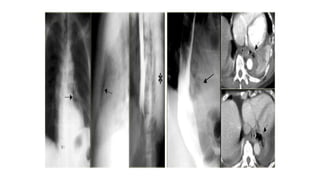

Leiomyomas

Leiomyomas are the most common benign esophageal

neoplasm and are often large yet nonobstructive.

Gastrointestinal stromal tumors (GIST) are least common in

the esophagus.

A calcified esophageal mass is almost always a leiomyoma.

On the left a patient with a calcified esophageal lesion

(arrows) protrudes into azygoesophageal recess on

Leiomyomas Leiomyomas are themost common benign esophageal neoplasm and are often large yet nonobstructive. Gastrointestinal stromal tumors (GIST) are least common in the esophagus.

A calcified esophagealmass is almost always a leiomyoma. On the left a patient with a calcified esophageal lesion (arrows) protrudes into azygoesophageal recess on radiograph.